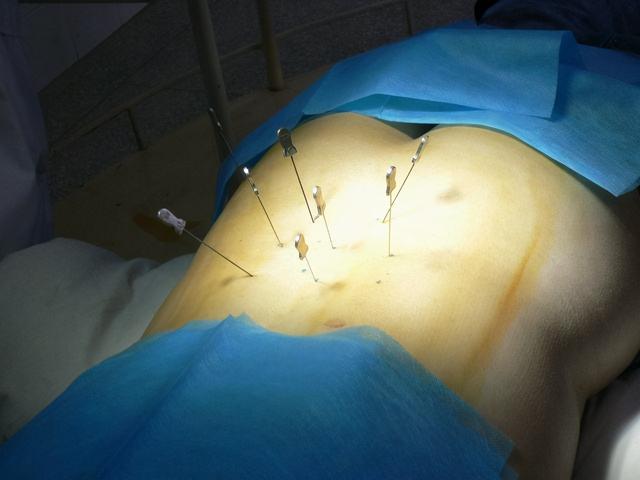

在治疗上我们一般分为两步,前中期我们采取保守治疗,通过物理疗法,也就是理疗之类的,在配合中药内服外敷进行调理,大多数腰间盘突出的患者都能慢慢的改善。如果到了后期,或者说保守治疗之后病情没有得到改善的时候,这时候可能出现大小便失禁等严重情况,我们需要考虑手术治疗,在手术治疗上我也有这很多年的手术经验。当然我们要尽量避免拖到后期,做好前中期的预防工作和积极的检查治疗,不要让腰间盘突出影响自己的生活。

腰间盘突出晚期患者手术治疗